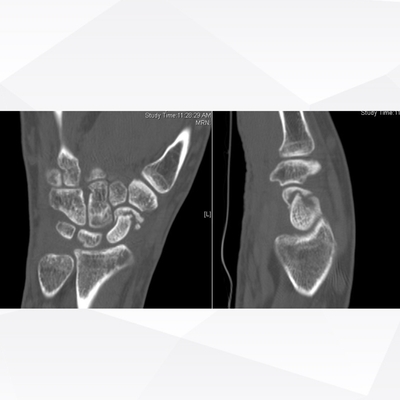

Click on an image below to view more info.